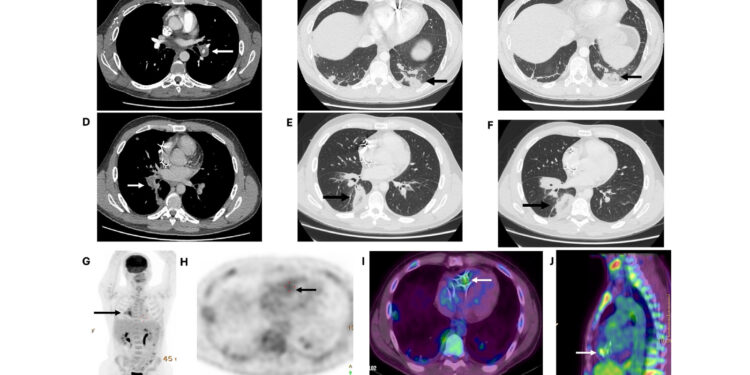

Advanced imaging eventually showed focal radiotracer…